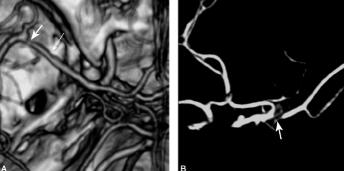

6月23日行CTA示:左侧大脑中动脉硬化,左侧大脑中动脉水平段不规则狭窄,膝部狭窄程度达重度(图4),左侧放射冠区脑梗死。

图4 2011年6月23日行颅脑CTA示:左侧大脑中动脉硬化,左侧大脑中动脉水平段不规则狭窄,膝部狭窄程度达重度;A.左侧大脑中动脉硬化,左侧大脑中动脉水平段不规则狭窄(细箭头),膝部狭窄程度达重度(粗箭头);B.左侧大脑中动脉膝部狭窄(箭头)